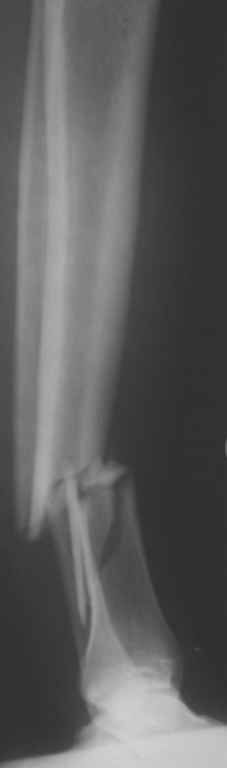

Уважаемые коллеги! Хотел-бы услышать Ваше мнение по поводу того, кто как относится к наличию свободных осколков в линии перелома и чем при этом руководствуется - размер, локализация, возраст и т.д.

Консультировал рентгенограммы после интрамедуллярного остеосинтеза бедра гвоздем Fixion. Пациенту объяснили, что важнее сохранить перелом "закрытым" чем фиксировать осколок из дополнительного разреза. Сами собираемся оперировать голень и думаем, что без "открытия" места перелома не обойтись.